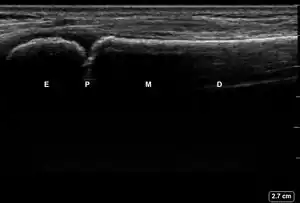

| 1 | No Fracture | "Unbroken" |

![]() Ultrasound lateral view of normal radius. E = epiphysis; P = physis; M = metaphysis; D = diaphysis. | |